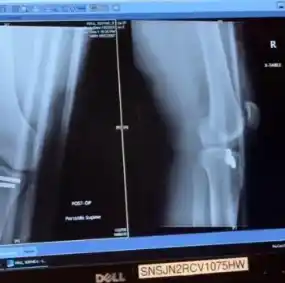

Por su parte, Hall exige un resarcimiento de 50.000 dólares por los daños físicos y psicológicos que le habría ocasionado el suceso. La modelo reveló que tuvo que someterse a una cirugía reconstructiva tras la fractura, lo que afectó su carrera profesional.

:format(webp):quality(40)/https://deporteglamcdn.eleco.com.ar/media/2025/02/la_foto_que_subio_la_modelo_en_sus_redes_sociales_de_la_rodilla_rota.png)